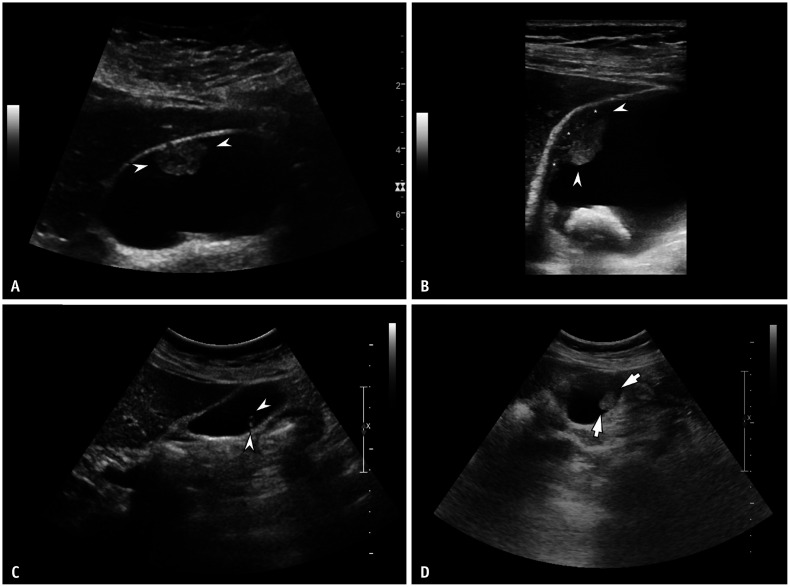

Abstract Image